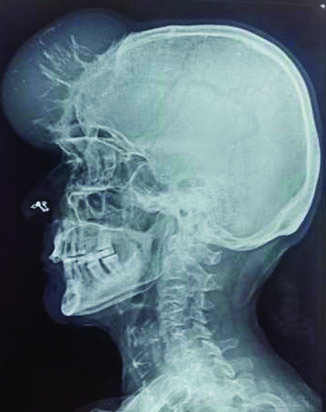

A 79-year-old female presented with swelling on the scalp associated with pain and blurring of vision since three months. The swelling was gradually increasing in size since the past eight months. On examination a single swelling was seen in the forehead region, extending on to the scalp, measuring 8x5 cm. Overlying skin appeared normal. The swelling was soft in consistency. X-ray of the skull showed an osteolytic soft tissue swelling with bony erosions in the frontoparietal region. The lesion was seen destroying the outer and inner table of the bilateral frontal and parietal bones, extending extradurally under the scalp [Table/Fig-1]. Fine needle aspiration, on repeated aspirates yielded haemorrhagic material. The smears were paucicellular, with cytological features favouring an adnexal tumour [Table/Fig-2]. Background showed large areas of haemorrhage.

X-ray of the skull showing an osteolytic legion in the fronto parietal region;